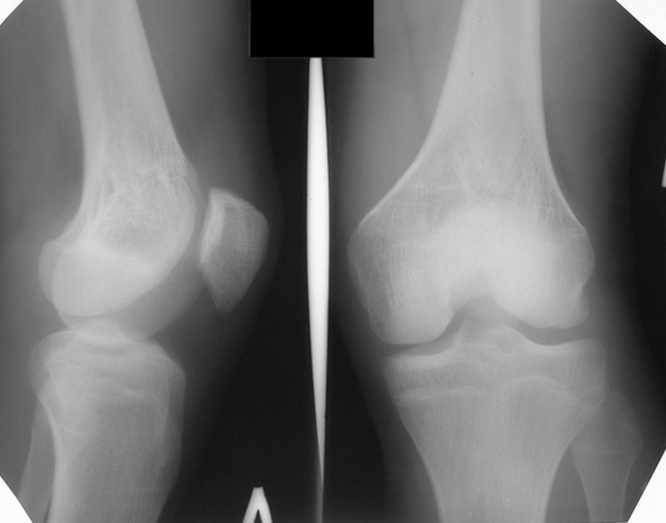

Больной Н., мужчина 18 лет с укорочением бедра и рекурвацией коленного сустава. Из анамнеза: огнестрельное сквозное пулевое ранение бедра 9 лет назад в н/3 левого бедра. Раны зажили без гнойных осложнений. Жалобы на укорочение левой нижней конечности и нестабильность в коленном суставе. При обследовании выявляется рекурвация коленного сустава. Абсолютное укорочение порядка 5см, стоя 8 см (за счет рекурвации). Имеется умеренный компенсаторный сколиоз. С передне-наружной стороны располагается рубец от входного отверстия, с задне-медиальной стороны от выходного. Можно предположить повреждение при травме зоны роста бедренной кости и задне-внутренних стабилизирующих структур коленного сустава. Предлагается обсудить тактику лечения: начать с удлинения бедра или со стабилизации коленного сустава, а также - на каком уровне производить удлинение бедра.A male 18 years old with shortened femur.Trauma 9 ears ago: gunshot wound with bullet of the left knee. It Is Reeked have healed without festering complications. The patient have shorter femur and recurvatum instability of knee joint. Absolute shortening is 5 cm, at standing up 8 cm (genu recurvatum). The input scar is situated on the antero-lateral side and output scar is on the postero-medial side. It is possible to expect damage by trauma of the growing zone of the femur and back-internal stabilizing structures of the knee joint. We discuss the treatment options: to begin with lengthening of the femur or preferably with stabilizations of the knee joint. What is the optimal level to produce the lengthening of the femur in this case.